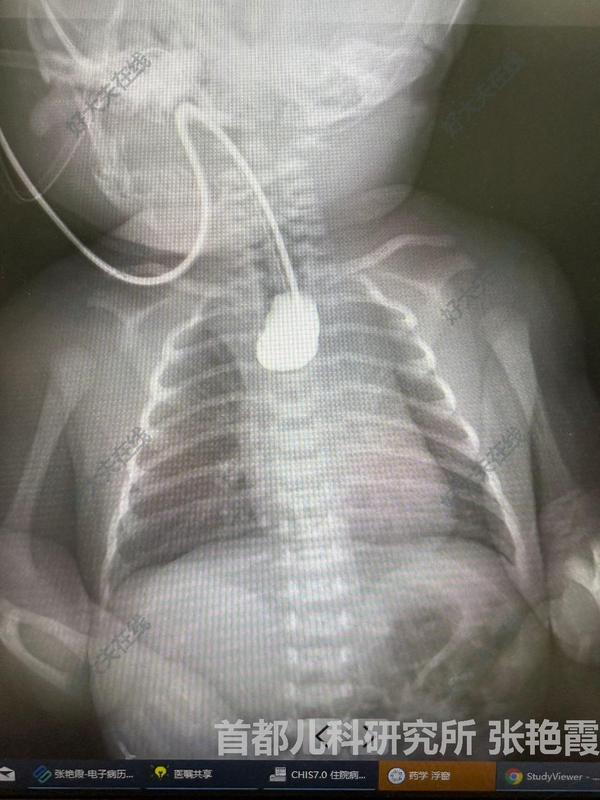

治療前產(chǎn)前診斷,出生后通過(guò)危重新生兒轉(zhuǎn)運(yùn)系統(tǒng)轉(zhuǎn)運(yùn)到我院,術(shù)前檢查明確3型食管閉鎖治療后治療后6月好你術(shù)后第一次造影,吻合口漏,通過(guò)床旁放置空腸營(yíng)養(yǎng)管保證腸內(nèi)營(yíng)養(yǎng),使吻合口能完全愈合。術(shù)后3周,吻合口完全愈合。術(shù)后6個(gè)月造影顯示食管無(wú)狹窄,無(wú)吻合口漏,如同原生狀態(tài)?;純荷L(zhǎng)發(fā)育與正常同齡兒無(wú)差別。